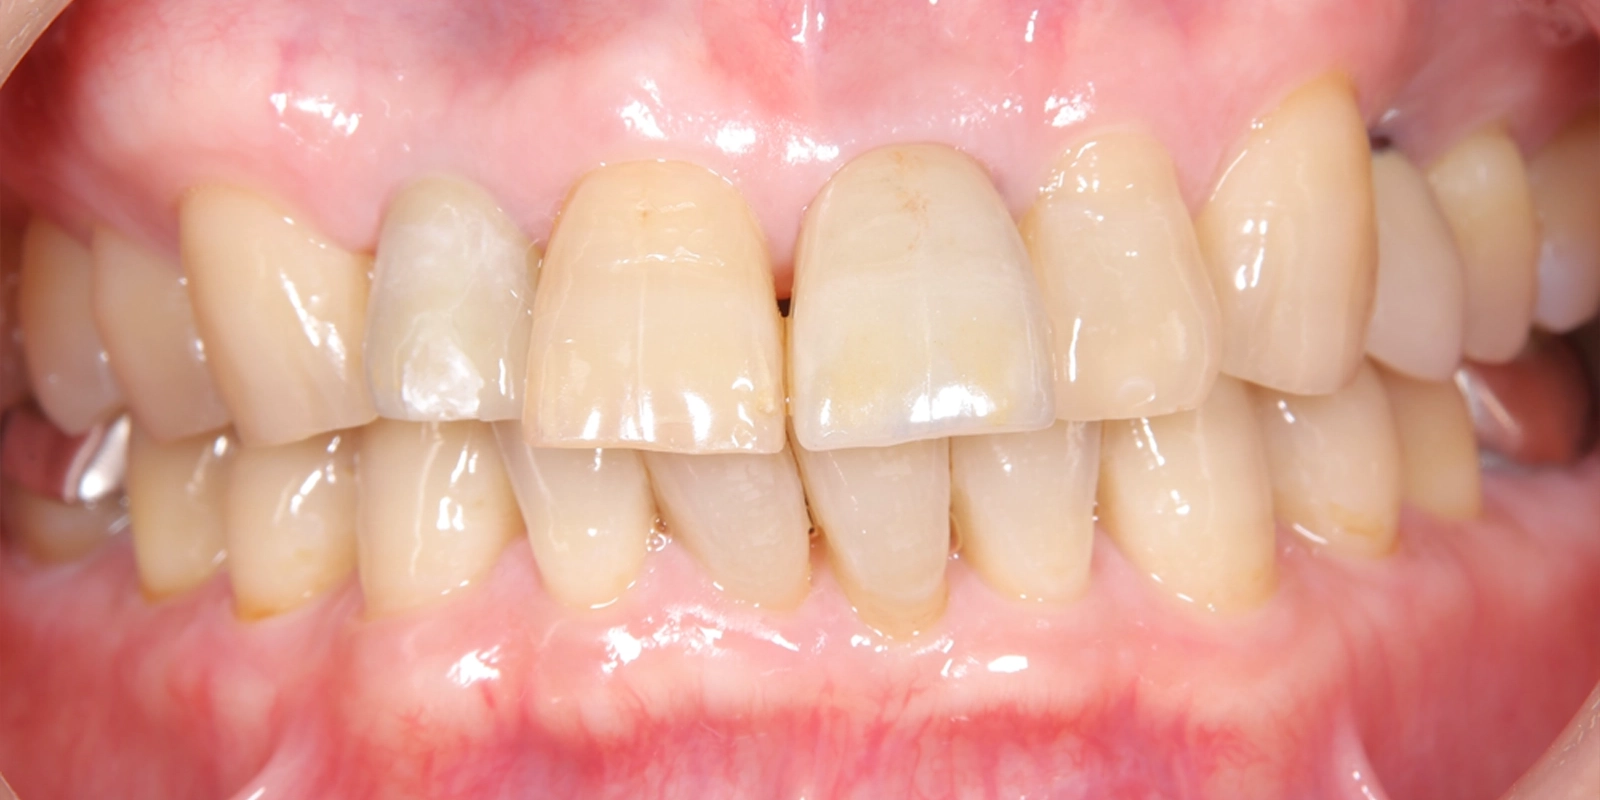

治療前の写真では、上顎前歯部の歯肉に広範囲にわたる赤みが認められます。

歯肉が腫れた状態が続いていたことで、歯と歯肉の境目のラインも乱れており、前歯全体として整った印象とは言いにくい状態でした。

治療後の写真と比較すると、歯肉の赤みが落ち着き、引き締まった状態になっていることがわかります。歯肉の境目のラインや色調も整い、前歯部として自然な見た目に近づいています。

インプラント周囲の歯肉が健康な状態で安定していることは、長期的な予後を考える上でも重要なポイントです。